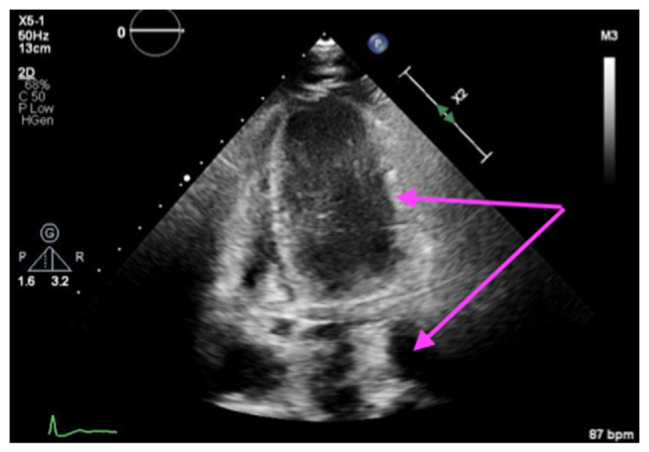

Case presentation: A 91-year-old woman with a history of coronary artery disease had undergone PCI in left anterior descending (LAD) and left circumflex artery (LCX) for a non-ST-elevation myocardial infarction (NSTEMI) 4 weeks prior at another facility, which was complicated by distal wire perforation leading to hemopericardium and the need for pericardiocentesis. She presented with chest pain, and her tests showed ST-segment elevation in leads I, aVL, V2-5, and ST-depression on III, avF, and high troponin levels which were concerning for stent thrombosis. Due to her age and multiple comorbidities, she was managed medically and her code status was changed to do-not-resuscitate/do-not-intubate (DNR/DNI) after family discussion. Echocardiogram revealed a severely reduced ejection fraction and a new mid-inferoseptal VSD detected on readmission. The patient died 4 days later, highlighting the critical importance of timely PCI to prevent severe complications like VSD.